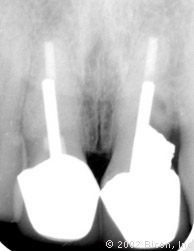

Рентгенограмма сразу после первого посещения

Две части: имплантант и абатмент. Никаких винтов и дополнительных креплений, которые создают условия для проникновения бактерий из-за неплотного прилегания частей конструкции.

Рентгенограмма спустя тринадцать недель после установки имплантантов Bicon

Плотный контакт «металл – металл» абатмента и стенок имплантанта обеспечивает надежную фиксацию и бактериальную непроницаемость соединения